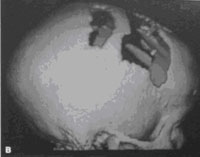

图7 三维重建CT

(图片来自于病案收藏)